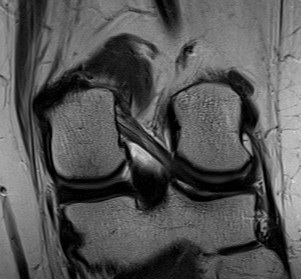

Medial meniscus anatomy

C shaped fibrocartilage

- posterior horn larger than anterior horn

- capsular attachment on the tibial side is the coronary ligament

- thickening of the capsule from tibia to femur is deep MCL

Lateral meniscus

Semicircular

- covers a larger surface of the tibia than MM

- anterior and posterior horns attach closer to each other

- anterior horn adjacent to ACL

- posterior horn behind tibial eminence

- ligaments of Humphrey and Wrisberg are attached to posterior horn

- popliteal hiatus posteriorly